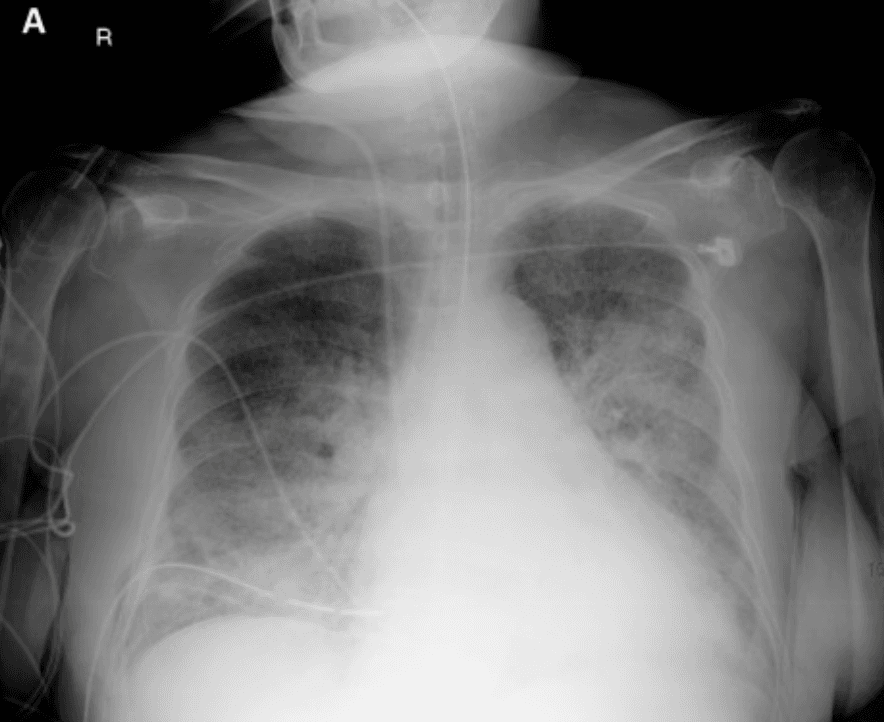

Two days before admsiion, he developed worsening cough, wheezing, and diffuse weakness. In the emergency department he became hypotensive and hypoxemic, requiring vasopressors and ICU transfer. Chest imaging shows bilateral patchy interstitial and alveolar infiltrates. Blood cultures later grow a gram-negative enteric organism.

Chest X-ray